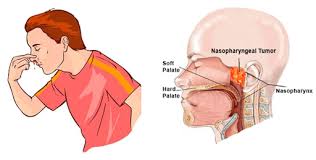

Overview

Package includes:

Days in hospital : 2 to 3 Days (For patient and one attendant)

Days in hotel : 5 Days (For patient and one attendant)

Room type in hospital : Shared

Room type in hotel : Private

Hotel category: Standard

Value added benefits of the Tonsillectomy:

Ø Doctor consultation charges

Ø Lab tests and diagnostic charges

Ø Room charges inside hospital during the procedure

Ø Surgeon Fee

Ø Nursing charges

Ø Hospital surgery suite charges

Ø Anesthesia charges

Ø Routine medicines and routine consumables (bandages, dressings etc.)

Ø Food and Beverages inside hospital stay for patient and one attendant.